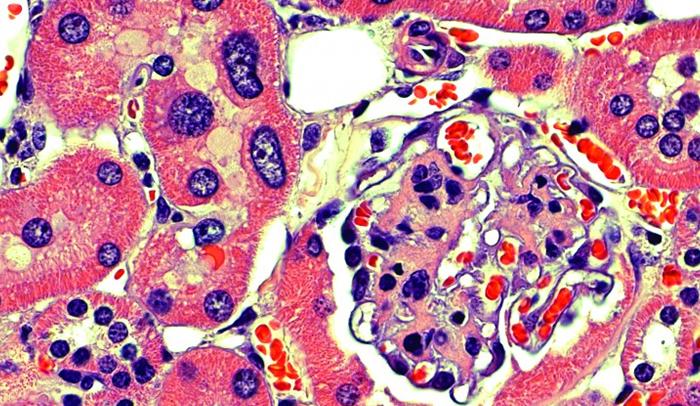

In humans, FAN1 deficiency causes karyomegalic interstitial nephritis, a disease that leads to kidney failure at around age 30. Thus far, the connection between the gene, which produces a DNA-cutting enzyme called a nuclease, and the kidney disease has remained obscure. The FAN1 knockout mice that Smogorzewska's lab has generated allow them to investigate the role of FAN1 in DNA repair, and to figure out how mutations in the gene may lead to kidney disease.

In observing kidney cells from the FAN1 knockout mice, the researchers noticed that their nuclei were abnormally large. This phenomenon, called karyomegaly, has also been seen in patients with karyomegalic interstitial nephritis, and it's thought to occur because the DNA duplicates too many times. The scientists saw these enlarged nuclei in the liver as well, and the mice developed liver dysfunction. They think the FAN1 protein helps protect liver function as the animals age.